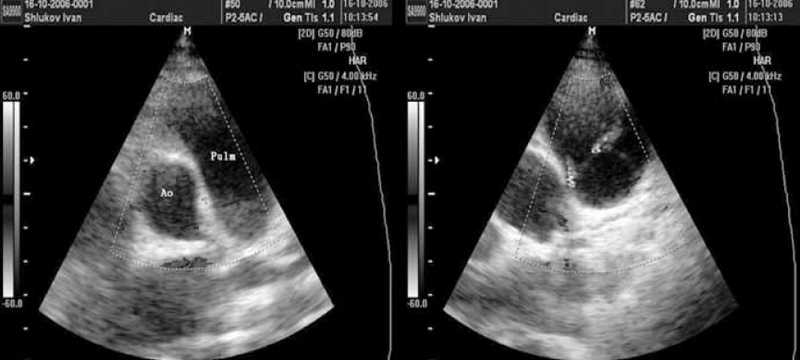

Аускультативная картина у обследованных детей с ОАП была чрезвычайно разнообразной (табл. 2). Классический машинный систоло-диастолический шум был выявлен лишь у 13 детей с ОАП (15 % от общего числа) (рис. 2).

Рис. 2. Исследование выполнено из левой парастернальной позиции по короткой оси. В зоне интереса ствол легочной артерии в режиме цветного допплеровского картирования. В синих тонах кровоток в легочной артерии «от датчика», в красных тонах кровоток через открытый артериальный проток «к датчику». Справа — допплерография в стволе легочной артерии — диагностируется систоло-диастолический сброс через открытый артериальный проток, сопровождающийся «машинным» шумом

У 70 % детей выявлялся лишь систолический шум во 2–3-м межреберьях слева у грудины, сопровождавшийся у половины из них акцентом 2-го тона над легочной артерией. Еще 15 % детей с ОАП вообще не имели значимых шумов над областью сердца (см. табл. 2).

В подавляющем большинстве случаев сброс крови из аорты в легочную артерию через ОАП визуализируется в стволе легочной артерии как поток красного спектра, направленный к датчику в левой парастернальной позиции по короткой оси (см. рис. 2). Сложности эхокардиографической диагностики и дифференциальной диагностики ОАП у детей могут быть обусловлены наличием других разнонаправленных потоков, визуализируемых в стволе легочной артерии, особенно в режиме цветового допплеровского картирования (рис. 3–6). Часть из них направлена «к датчику» и окрашивается в красные цвета, другие направлены «от датчика» и визуализируются как потоки синего цвета. Таким образом, высокоскоростные патологические потоки из аорты в легочную артерию через открытый артериальный проток и аортолегочную фистулу имеют направление «к датчику» и окрашиваются в цвета красного спектра. Низкоскоростные потоки из бассейна коронарных артерий в легочную артерию через коронарные фистулы чаще окрашиваются в синие цвета «от датчика» (см. рис. 3–5).